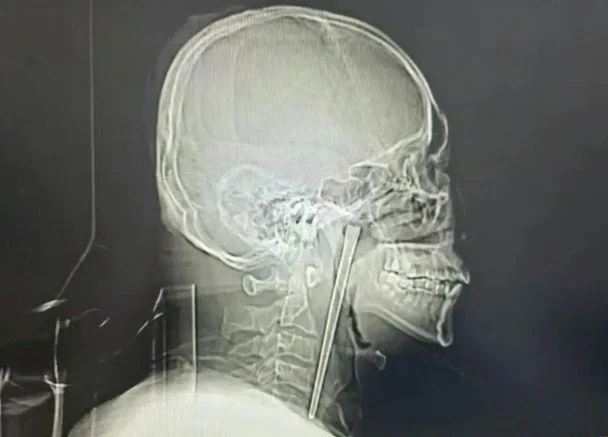

Хятадад нэгэн эр хоолойндоо тээглэсэн 12 см урт төмөр саваатай найман жилийн турш амьдарсан бөгөөд саяхан л мэс заслын аргаар авахуулжээ. Энэ талаар SCMP мэдээлсэн байна.

Уг хэрэг Ляонин мужийн Далянь хотын төв эмнэлэгт хүргэгдсэн Ван овогтой эртэй холбоотой юм. Эмч нарын мэдээлснээр, төмөр саваа найман жилийн өмнө хоол идэж, согтууруулах ундаа хэрэглэж байх үед нь хоолойд нь оржээ. Тухайн үед эр өвдөлт мэдэрсэн ч амьсгалахад хүндрэл үүсээгүй тул үүнийг ноцтой зүйл гэж үзээгүй байна.

Шинжилгээний явцад эмч нар зөөлөн тагнай орчимд гаднын биет байгааг илрүүлжээ. Удаан хугацаанд байсан ч саваа ноцтой гэмтэл учруулаагүй бөгөөд дууны хөвч хэвийн ажиллаж, эргэн тойрны эдүүд харьцангуй бүтэн үлдсэн байв.

Өвчтөний хүсэлтийг харгалзан эмч нар хүзүү зүсэхгүйгээр амаар орж, бага зүслэгтэй мэс засал хийжээ. Ингэснээр 12 см урт төмөр савааг амжилттай авч чадсан байна.